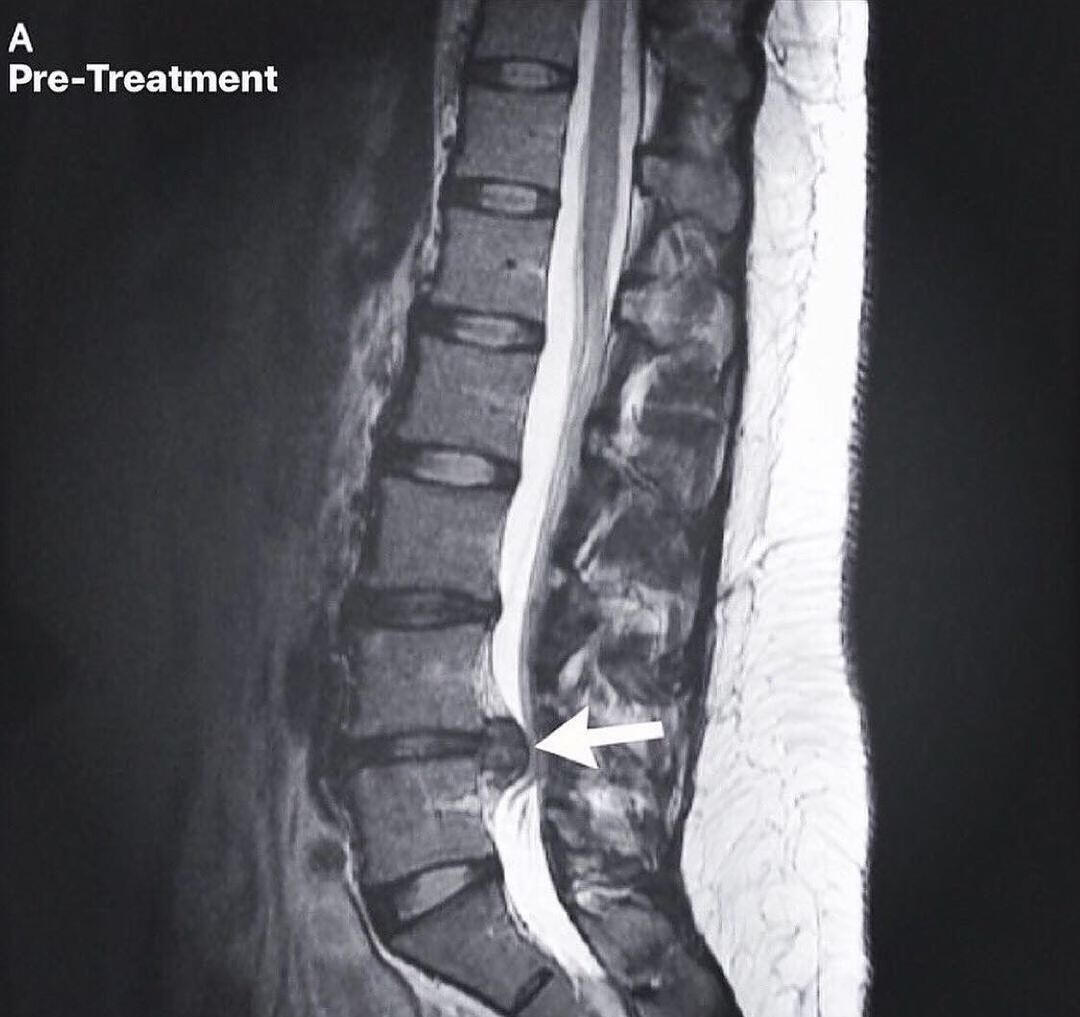

Spinal Disc Rehabilitation in Inver Grove Heights

Advanced care for disc injuries, herniations, and chronic spinal conditions

Spinal disc injuries require more than symptom-based care. Our spinal disc rehabilitation approach in Inver Grove Heights focuses on restoring movement, reducing pressure on the disc, and improving how the spine and nervous system work together over time. Care is guided by imaging, clinical findings, and measured progress, not guesswork or force.This care is designed for people dealing with disc herniations, disc bulges, sciatica, chronic back or neck pain, and those who have not improved with traditional chiropractic care. It is also appropriate for individuals looking for non surgical disc care before considering injections or surgery.